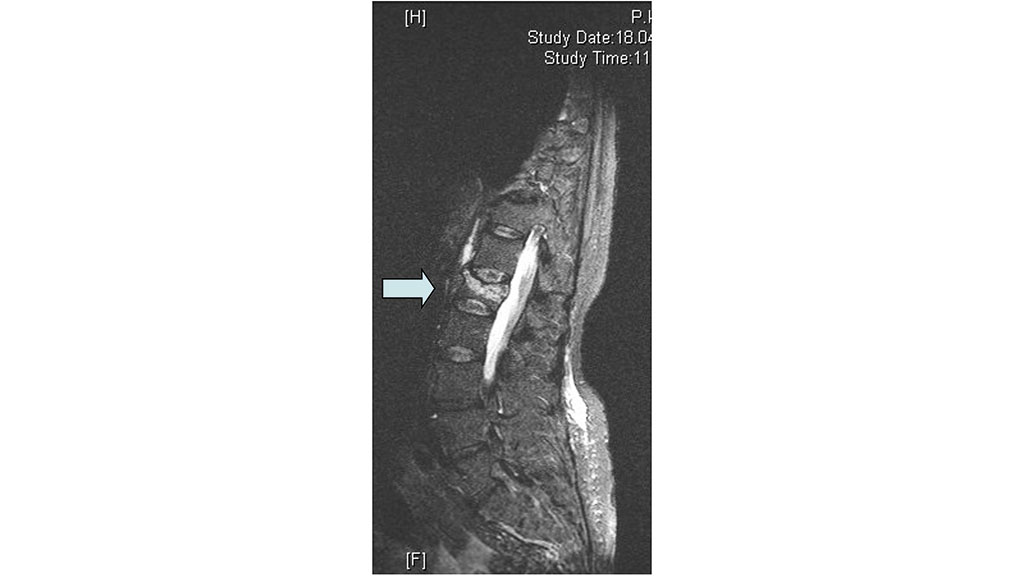

Bildgebende Standarddiagnostik ist die nativradiologische Darstellung des betroffenen Wirbelsäulenabschnittes in zwei Ebenen. Bei diagnostizierter Fraktur (Abb. 1) sollte bei Verdacht auf eine alte Wirbelkörperfraktur zusätzlich nativradiologisch eine Hypomochlionaufnahme (Abb. 2) im Liegen angefertigt werden, um erste Hinweise auf eine mögliche Wirbelkörperpseudarthrose zeitnah zu erhalten. Weiterführend wird mittels Magnetresonanztomografie (MRT) geklärt, ob es sich um eine frische Fraktur handelt (Steigerung der Intensität in den STIR- oder TIRM-Sequenzen) (Abb. 3) und ob möglicherweise ligamentäre Strukturen verletzt sind, um eine mögliche B- oder C‑Verletzung (nach AO: Arbeitsgemeinschaft Osteosynthese) der Wirbelsäule nicht zu übersehen. Gegebenenfalls wird die Diagnostik mittels Computertomografie (CT) vervollständigt, um die Frakturform exakt evaluieren und klassifizieren zu können. Echte Operationsindikationen sind Berstungsfrakturen der Wirbelkörper sowie B- und C‑Verletzungen der Wirbelsäule 22.